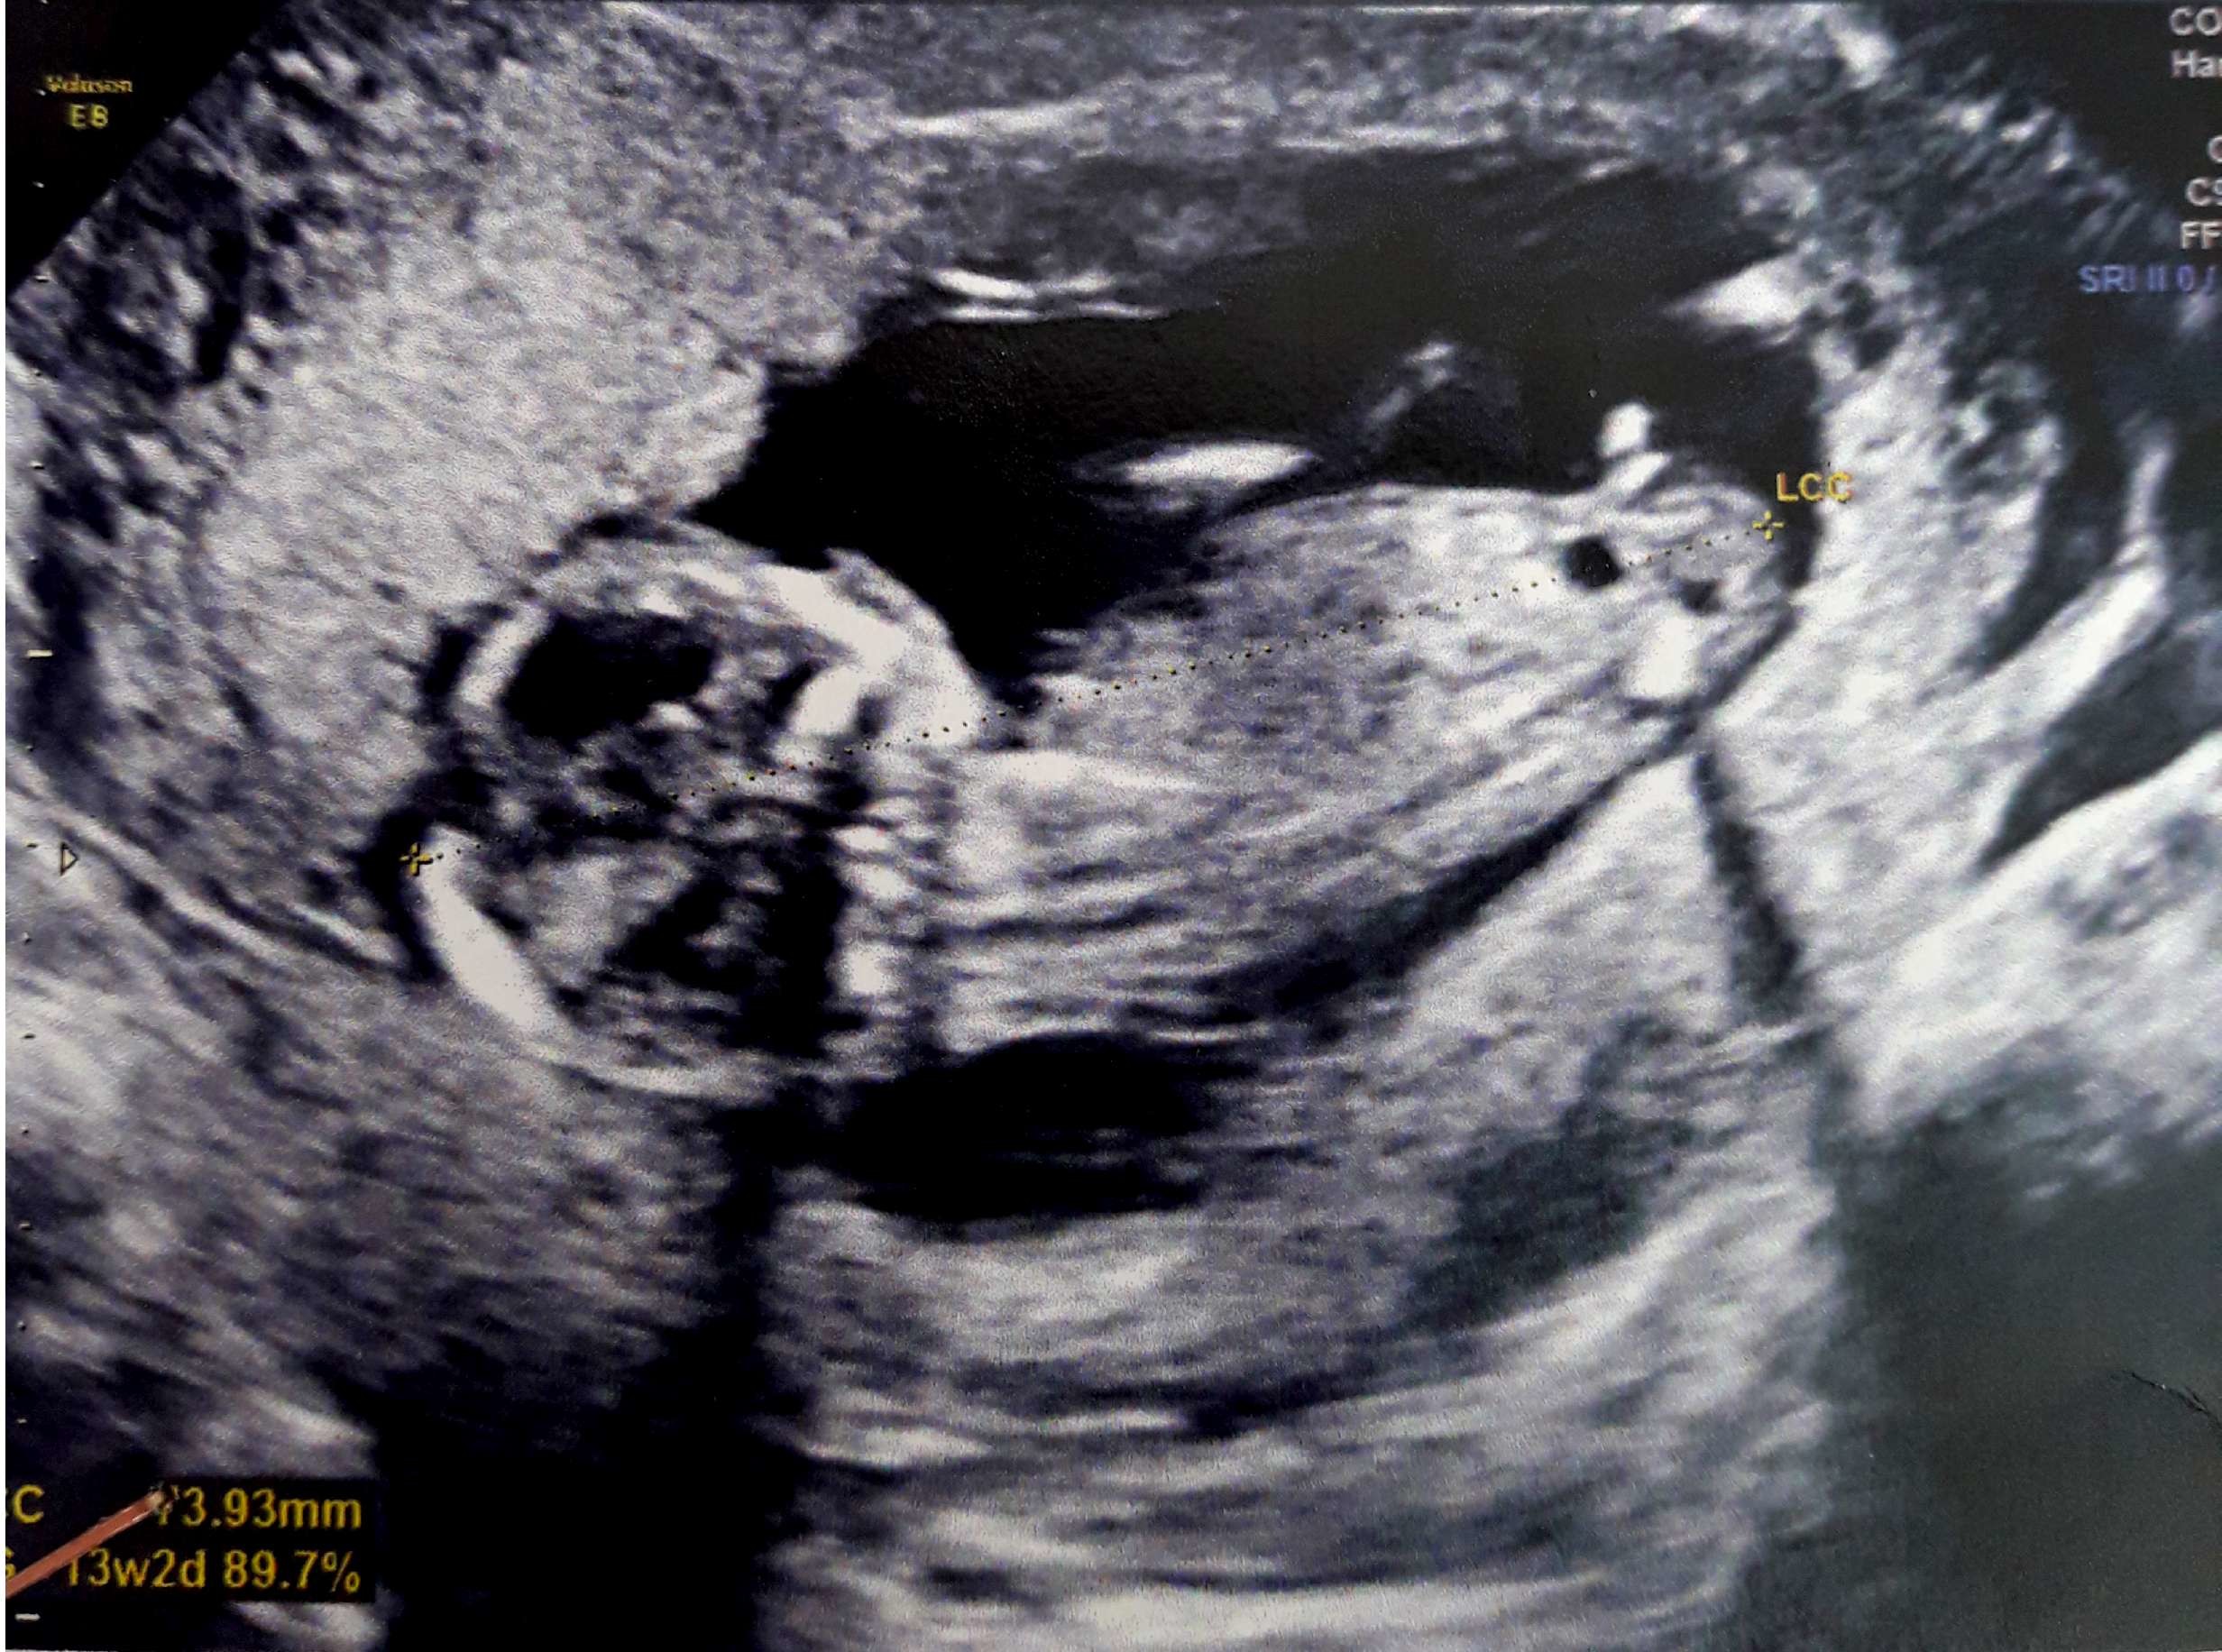

at 856 am ET on 247WallStcom This Top Beer Maker Is Going to Produce Cannabis Beverages This Year at 812 am ET on Motley FoolL'aspect est celui d'une fille quand les deux droites ne se rencontrent pas Le taux d'erreur est de 0,9% 3 % Dans toutes les séries il y a plus d'erreurs quand on annonce une fille L'aspect est celui d'un garçon quand l'angle ainsi tracé est supérieur à 30° Le taux d'erreur est de 0,2%J'ai eu mon écho des 13 SA et gygy m'a fait un pronostic de sexe en voyant le tubercule génital de dessous (bébé est de dos) je pensais qu'on pouvait mieux voir de profil

Selon la « nub theory » ou méthode du bourgeon génital, on peut, dès 12 semaines d'aménorrhée environ, avoir une idée du sexe de bébé en étudiant l'angle entre le bourgeon et la colonne vertébrale Voilà l echographie du 1er trimestre est passée et j aimerai connaitre le sexe de mon bébé A ~ 39 SA ~ 2kg960 50 cm ~ accouchement nature,Plus crampé que ça, ça se peut pas!!!Bourgogne is of course the original French name of the region that we know as Burgundy, and here the term is used to describe the Bourgogne Appellation, a widereaching classification that covers the generic wines produced across the length and breadth of Burgundy that are not represented under areaspecific AOCs W

Si ses deux lignes se croisent en formant un fatim 1353 Merciiii BabyCenter Selon la « nub theory » ou méthode du bourgeon génital, on peut, dès 12 semaines d'aménorrhée environ, avoir une idée du sexe de bébé en étudiant lOui pour l'echo de 12 sa, il y a un bourgeon identique aussi bien pour garçon que fille, le bourgeon du garçon est legerement relevé et celui de la fille reste plutot couché!Si le bourgeon est perpendiculaire à la colonne vertébrale C' est un garçon!

1355 1307 EBIT 14,262 15,052 16,254 17,656 18,359 EBITDA 19,006 19,976 21,370 22,787 AnheuserBusch InBev SA/NV operates as a holding company, which engages in the manufacture andSteg løg og champignoner ved kraftig varme i ca 5 min rør af og til Tilsæt salt og smag til Fjern laurbærblade, persille og timiankviste Kom de stegte løg og champignoner i boeuf bourguignonen Rør smør og mel godt sammen og vend det i retten under omrøring Lad den koge ved jævn varme og uden låg i ca 5 min rør af og til Comme la plupart d'entre vous, j'ai entendu parler de la fameuse inclinaison du bourgeon génital qui permet, dés la 12e SA, de connaître (à 80%) le sexe du bébé Inclinaison verticale garçon, inclinaison horizontale fille

Ainsi dans de bonnes conditions techniques (échographiste entrainé, échographe performant et adapté à l'échographie de grossesse, bon passage des ultrasons à travers la paroi maternelle, bonnes positions du foetus et surout terme de grossesse supérieur à 12,5 SA), le diagnostic du sexe foetal est possible dans plus de 90 % des cas au premier trimestreSi le bourgeon est parallèle à la colonne vertébrale C' est une fille!Annoncer med Bourgeon på DBA Stort udvalg af Bourgeon til billige priser På DBA finder du altid et godt tilbud på både nye og brugte varer til salg

Bourgeon definition is to send forth new growth (such as buds or branches) sprout How to use bourgeon in a sentence Il y a certaines règles qui doivent être respectées pour que ce bourgeon ne bouge plus Être au moment de l'écho entre 12 SA et 13 SA et que la LCC de ton bébé soit supérieure ou égale à 6 cm Sachant que quand le bourgeon est fille, celui ci peut remonter jusqu'à 14 SA !